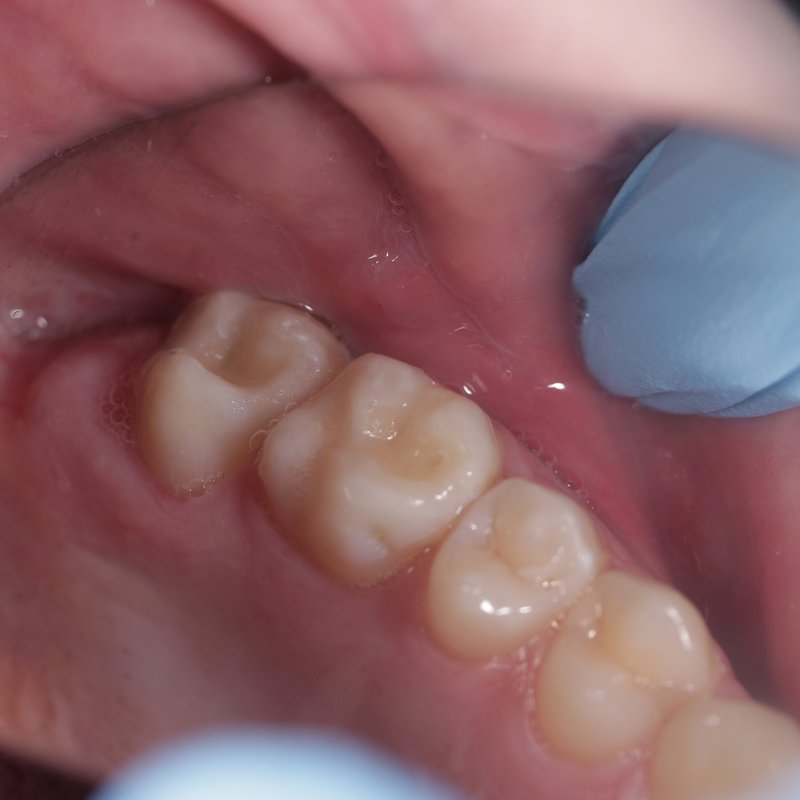

Фотогалерея